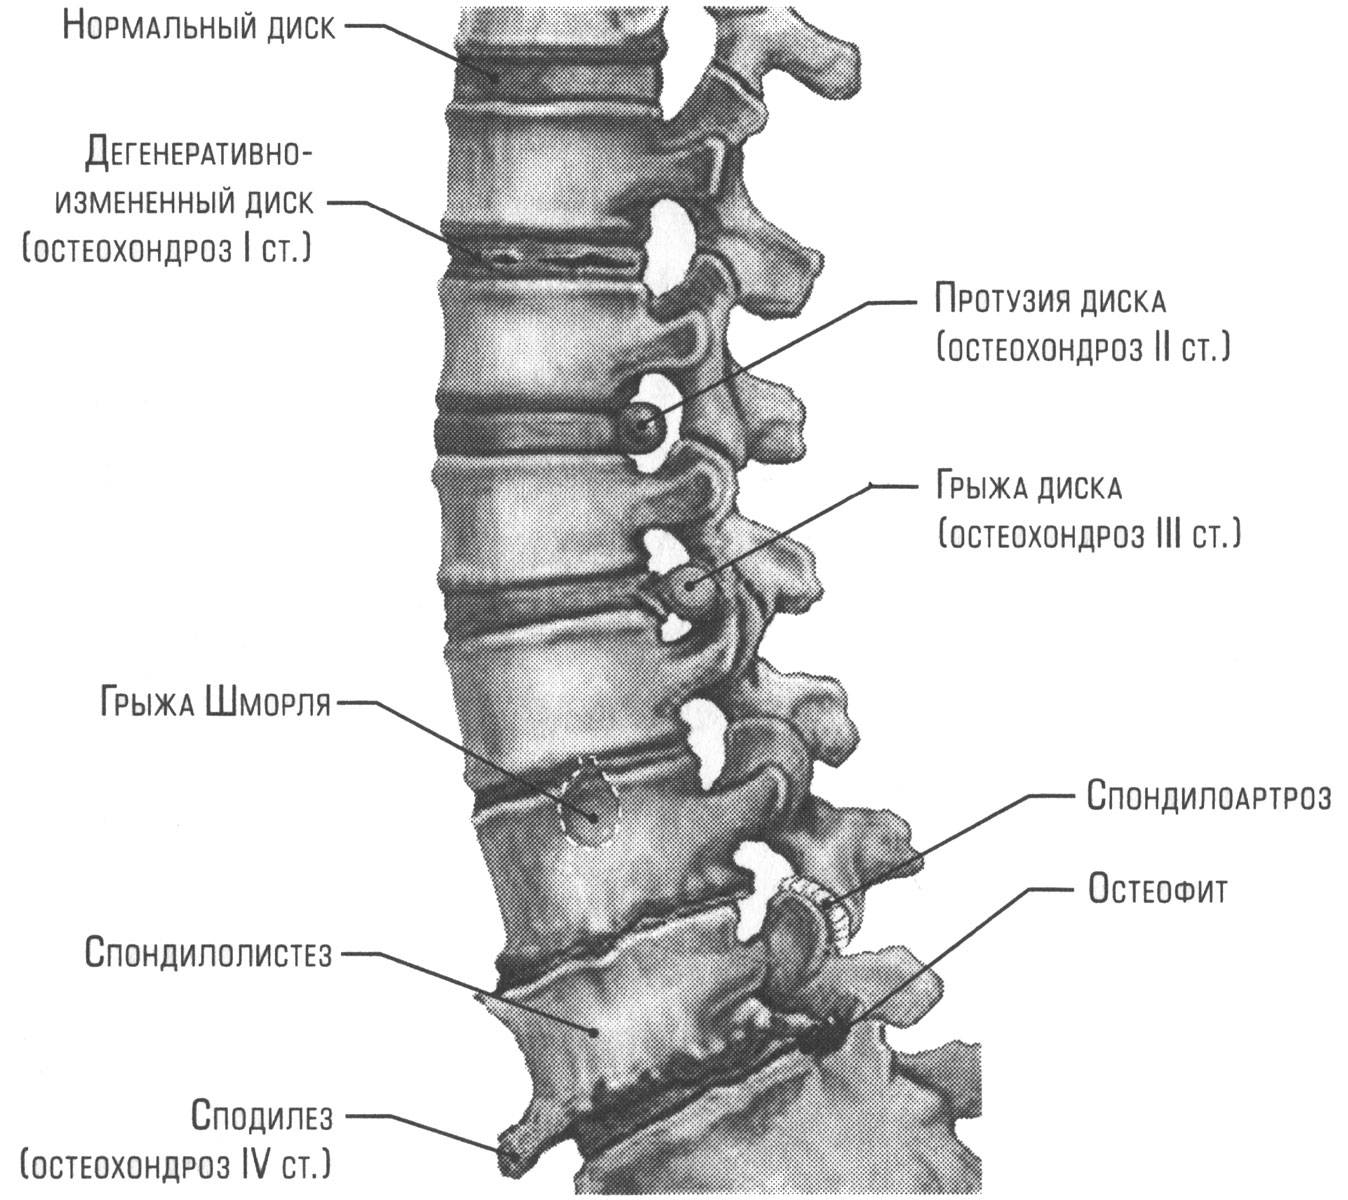

Мрт картина дегенеративно дистрофических изменений пояснично крестцового отдела позвоночника